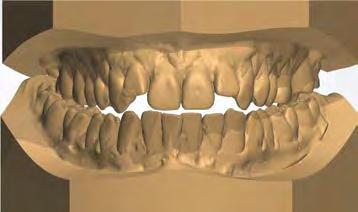

–Corticotomías y Ortodoncia. Ampliando límites del movimiento dental, por la Dra. Aranzazu Senosiain y cols. [50]

–Tratamiento de un caso de Ortodoncia y Cirugía Ortognática con placas preformadas y tecnología 3D, por la Dra. Elena Bonilla Morente y cols. [62]

–Uso del anclaje esqueletal como alternativa eficiente en el manejo ortopédico de clases III por deficiencia de maxilar superior, por el Dr. Carlos Becerra y cols. [74]

–MARPE, una alternativa a la disyunción en el paciente adulto, por el Dr. Enrique Solano y cols. [88]